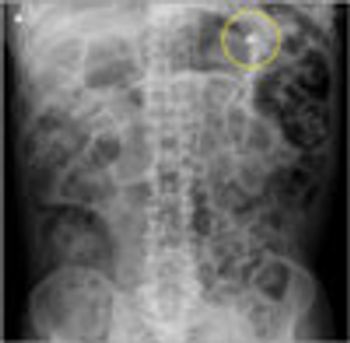

We describe a patient with intravascularpulmonary lymphomawho presented withprogressive dyspnea and hypoxemiawith normal chest radiographicfindings. After anunrevealing noninvasive evaluation,a high-grade B-cellintravascular lymphoma wasdiagnosed by bronchoscopywith transbronchial biopsy.Treatment with a modifiedCHOP regimen resulted in resolutionof the patient’s hypoxemiaand exercise limitation.Although intravascular pulmonarylymphoma rarely presentswith pulmonary symptoms,it should be consideredin the differential diagnosis ofpatients presenting with hypoxemiaand normal chest radiographicfindings.